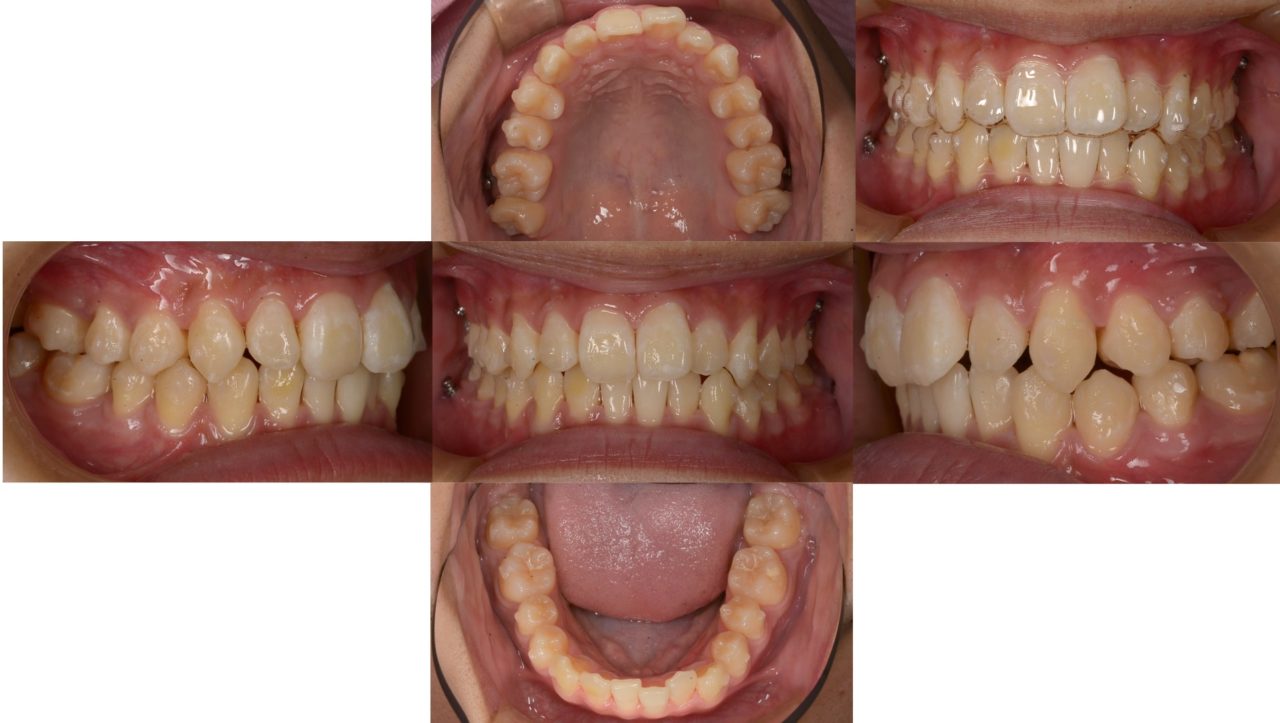

After

2024.10.30 矯正治療終了

動的矯正治療終了